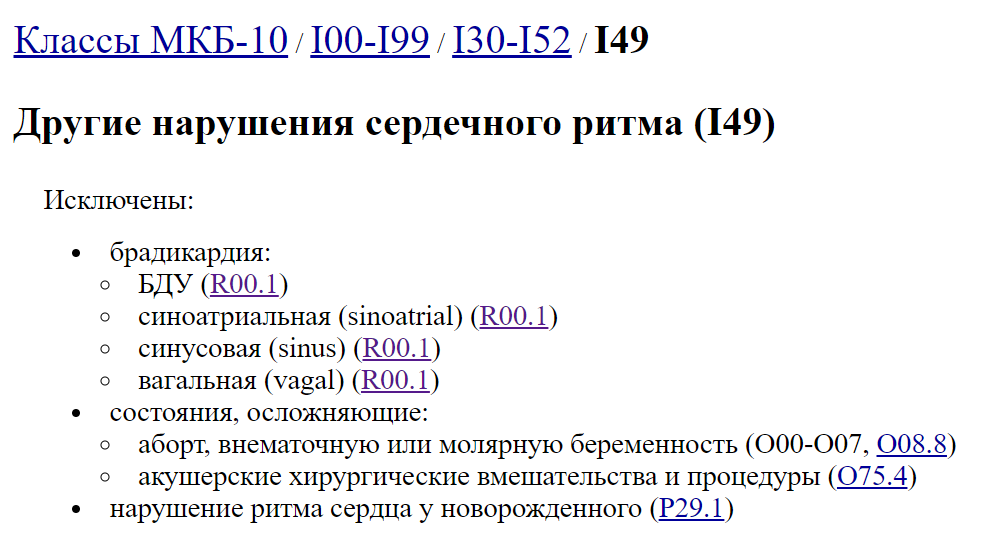

Код мкб 10 атерома головы

Код мкб 10 атерома головы 109 фото